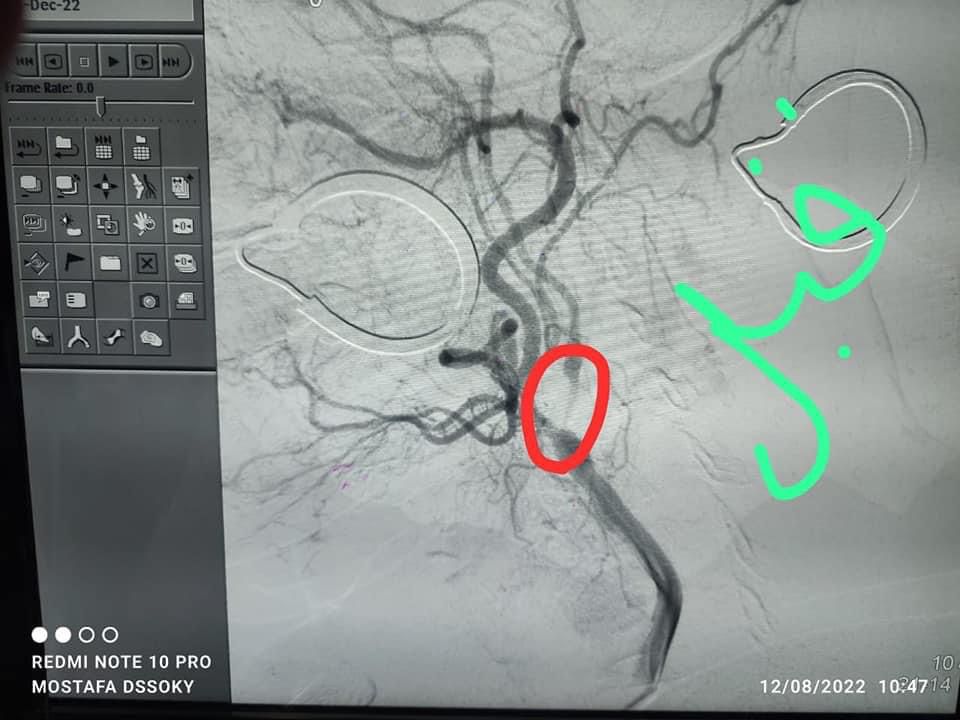

مستشفى قنا العام ينجح في إجراء قسطرة مخية لـ مُسنة 70 عاما

نجح فريق طبى بمستشفى قنا العام، اليوم الخميس، فى إجراء عملية قسطرة مخية لمريضة تبلغ من العمر 70 عاما، وتعرضت لجلطات متكررة من قبل، تحت إشراف الدكتور راجي تاوضروس، وكيل وزارة الصحة بقنا، والدكتور محمد الديب، مدير المستشفى.

وقال الدكتور محمد الديب، إن الفريق الطبي نجح في إجراء عملية ناجحة لمريضة تبلغ من العمر 70 عاما تعرضت لجلطات متكررة في المخ وعانت من ضيق أكثر من 95%، جرى خلالها توسيع الشريان باستخدام بالونة، وتم وضع دعامة للشريان.

و أشار مدير مستشفى قنا العام، إلى أن حالة المريضة جيدة وخرجت في نفس اليوم، بعد تماثلها للشفاء.

وأوضح الديب، أن الفريق الطبي تكون من الدكتور إسلام المالكي، مدرس المخ والأعصاب والقسطرة المخية بكلية الطب، الدكتور أشرف أمين، استشارى طب الحالات الحرجة ورئيس قسم العنايه المركزة.

وأضاف مدير مستشفى قنا العام، أن الفريق الطبى عاونه فريق من هيئة التمريض ضم كلا من: مصطفى الدسوقى، مشرف الوحدة وشيماء عنتر ومنى ورقية محمد وفني الأشعة أحمد الحايس.